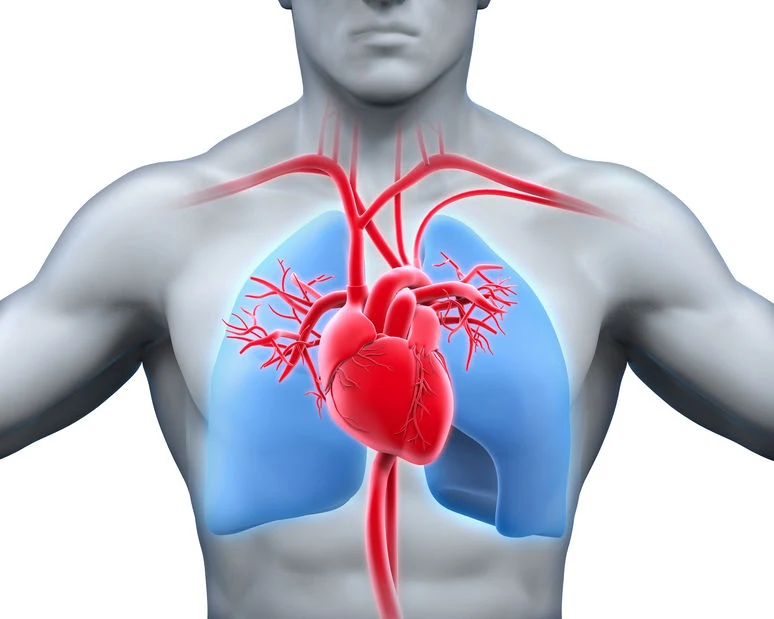

Kołatanie serca to dolegliwość, która zawsze wzbudza pewien niepokój. Najczęściej kojarzymy ją z chorobami układu krążenia i wadami serca. I rzeczywiście – przyspieszone i niemiarowe bicie serca może być objawem chorób mięśnia sercowego, takich jak migotanie i trzepotanie przedsionków, choroba niedokrwienna czy niewydolność serca. Warto jednak wiedzieć, że w ten sposób ujawniają się też inne schorzenia – przede wszystkim nerwice i zaburzenia lękowe, nadczynność tarczycy, a nawet refluks żołądkowo-przełykowy. Kołatanie serca może też być spowodowane gwałtownymi zmianami hormonalnymi, anemią, a także zaburzeniami elektrolitowymi. Jego powikłania mogą nawet doprowadzić do udaru mózgu. Sprawdź, kiedy kołatanie serca może być niebezpieczne i o czym świadczy.

Kołatanie serca to charakterystyczny objaw chorób tego narządu. Zaburzenia rytmu serca mogą być spowodowane wadami wrodzonymi, zapaleniem osierdzia czy niewydolnością serca. Zazwyczaj towarzyszą im też inne symptomy: bóle w klatce piersiowej, przyspieszony oddech, zawroty głowy, wysokie ciśnienie i puls (ponad 100 uderzeń na minutę). W takiej sytuacji należy jak najszybciej wezwać karetkę pogotowia.